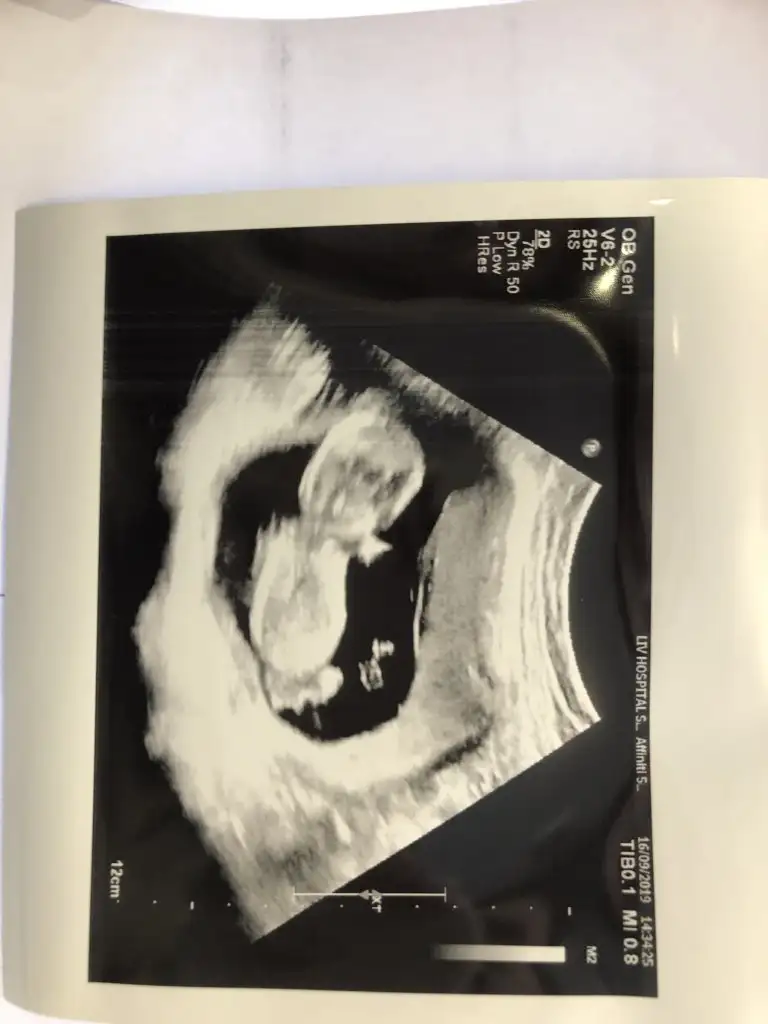

13+4 nub olmaz 11 yada 12 hafta olmalı kafa şekli kız ama tutmaya bilirMerhaba benim için de anlayan birisi tahminde bulunabilir mi? 13+4 haftalık hamilelik.

Teşekkür ederim cevap verdiğiniz için. Eve gittiğimde daha eski ultrason görüntüsü var mı bakıp yükleyeceğim. Doktor da kıza benziyor dedi fakat çok da net değil biraz daha bekleyelim dedi. Ben de merak ediyorum.13+4 nub olmaz 11 yada 12 hafta olmalı kafa şekli kız ama tutmaya bilir